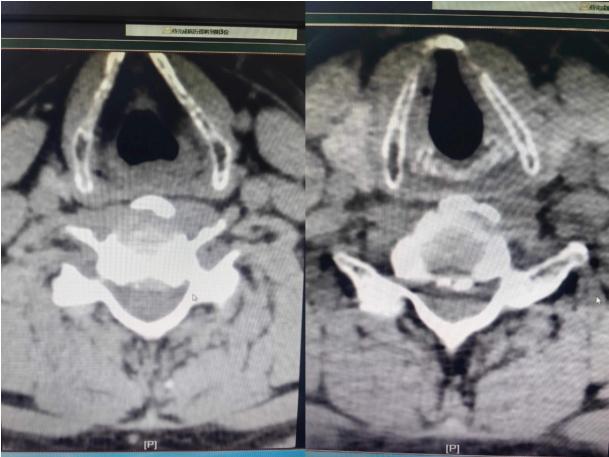

据悉,患者为男性,现年50岁,因颈肩部疼痛伴右上肢牵扯疼痛30年,于11月19日到新利官网登录康复医学科就诊。患者自诉夜间疼痛加重影响睡眠,曾为其开展颈椎间盘射频消融术,但效果不明显。该患者入住康复医学科时,VAS(疼痛等级)评分5分。颈椎CT提示:1.C5/6、C6/7椎间盘向后突出2-3mm;2.颈椎退行性变。诊断为:神经根型颈椎病。为恢复患者身体健康,改善患者生活质量,康复医学科结合患者病史、症状、体征及辅助检查,制定了详细的诊疗计划,并于患者入院后第三天为其开展肌骨超声引导下选择性颈神经根、腋神经注射治疗术。在康复医学科住院医师杨欣和超声科副主任医师乔永琼的通力合作下,历经1小时紧张有序的诊治,本次治疗取得圆满成功。术后,患者上肢放射痛明显缓解,VAS评分2分,患者及家属对本次治疗的效果非常满意。